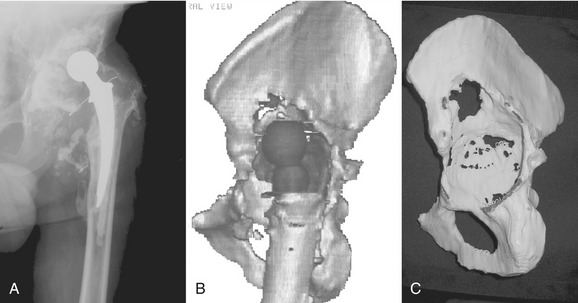

A standard CT scan of the pelvis with or without implants in place with 3-mm cuts from the anterior superior iliac spine to the obturator foramen and 5-mm cuts for the remainder of the pelvis is obtained. The uncompressed data are then recorded on a CD-ROM and sent to the implant manufacturer. The manufacturer (Biomet or DePuy, Warsaw, IN) will provide detailed instructions on surgeon request. Metal subtraction software is used to create a three-dimensional, one-to-one model of the hemipelvis for the surgeon to analyze (Fig. 51-1). The engineers rely on markings of the flanges made on the pelvic model by the surgeon, and a clay prototype of the component is subsequently prepared. The head center location is chosen based on patient-specific considerations, including leg length discrepancy, planned retention or revision of the femoral component, length of contralateral leg, and size of the current acetabular component and should be specified in the initial order. Generally, the vertical head center location is established by first determining the approximate anatomic position of the head center using the superior aspect of the obturator foramen as a reference point. The remaining bone of the anterior and posterior columns determines the head center in the coronal plane, whereas the flange geometry and component face diameter guide the position of the head center in the sagittal plane. The component face orientation is established by setting the abduction and anteversion angles of the cup. The abduction angle is established using the plane of the obturator foramen as a reference. The anteversion angle is established using the plane of the iliac wing and the obturator foramen as references.